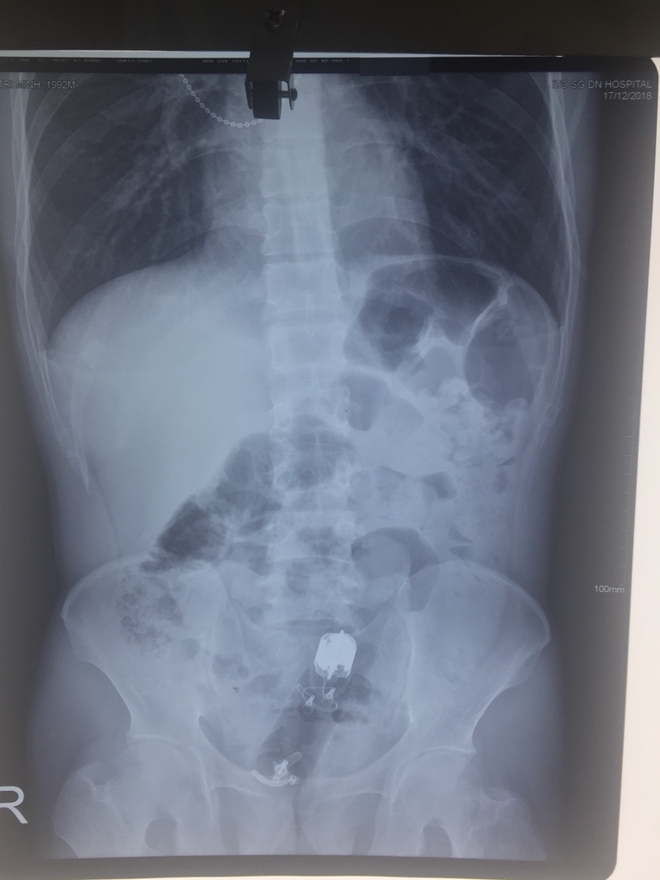

Hình chụp X- Quang dị vật nằm trong trực tràng bệnh nhân. |

Qua chụp X Quang và nội soi, các bác sĩ phát hiện, một dị vật đã chui sâu vào trong trực tràng của người đàn ông sâu tới 10cm và xác định sẽ rất khó lấy ra.